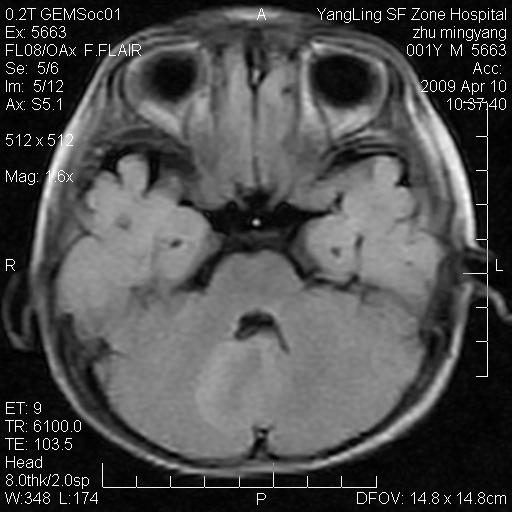

患者:1岁半,两天前外伤收住我院,ct检查小脑占位

考虑星形细胞瘤,建议增强

髓母细胞瘤或血管母细胞瘤,增强后可以鉴别;影像资料见 <。鱼博浪老师的《中枢神经系统ct与mr鉴别诊断》 小脑部肿瘤章节。

髓母细胞瘤或血管母细胞瘤!支持!

支持考虑髓母细胞瘤

考虑----髓母细胞瘤可能性大

考虑髓母细胞瘤或室管膜瘤。

支持髓母细胞瘤。

考虑髓母细胞瘤。

考虑髓母细胞瘤或星形细胞瘤

考虑髓母细胞瘤.

考虑髓母细胞瘤可能性大。

小脑肿瘤.考虑髓母细胞瘤可能.

就病灶部位及临床资料首先考虑髓母.